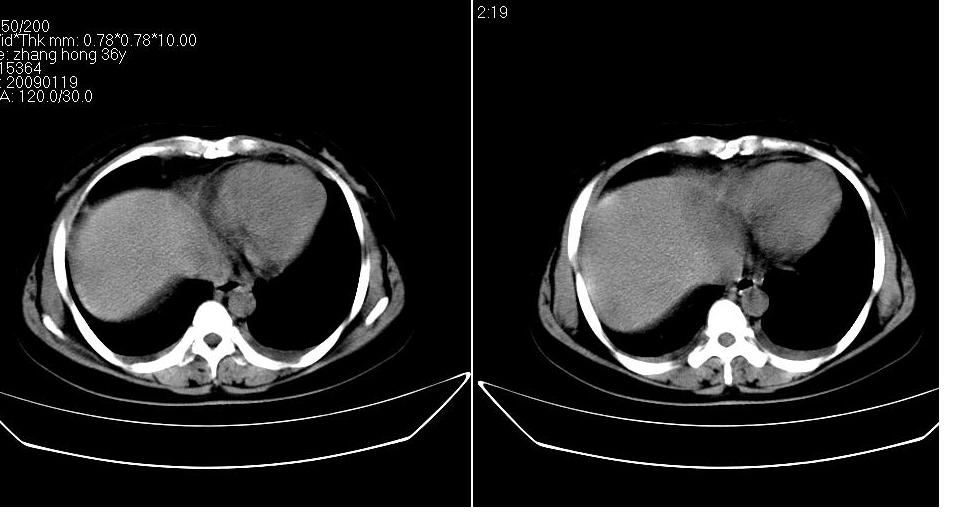

女 36岁,腹痛月余,b超提示肝左叶占位,腹水。

肝脏左叶明显增大,各叶比例失调,左叶实质内不均匀低密度影,似乎有肝内胆管的扩张,没有增强实在不好判断,不知患者肝功能是否正常,我觉得象胆管细胞癌。

1)考虑肝左叶肝癌;建议行进一步检查。2)肝硬化,脾稍大。3)双侧少量胸腔积液。

肝左叶占位,建议增强。胸腔积液。